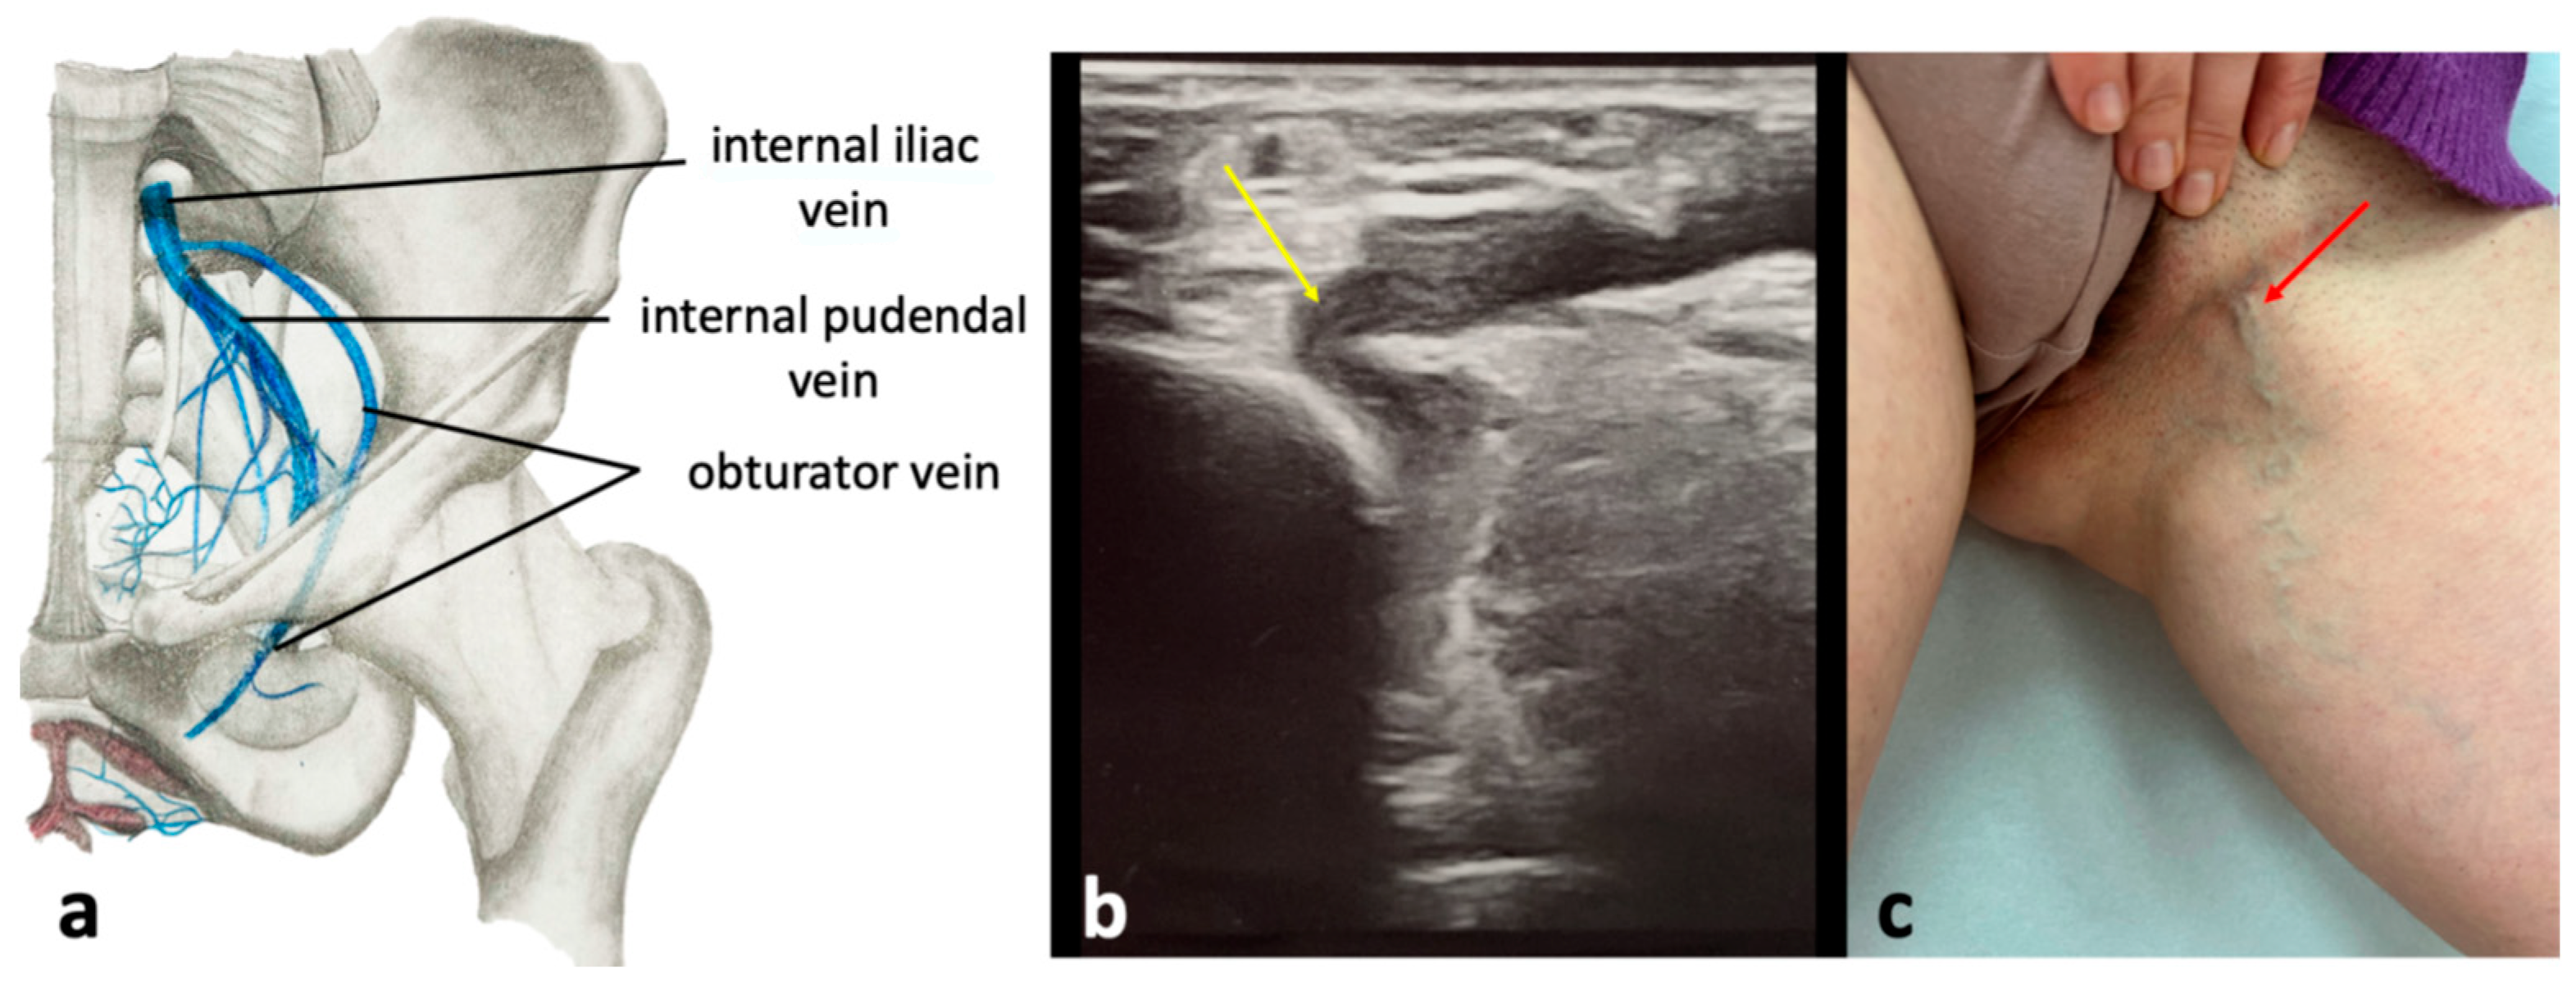

These pelvic escape points are associated with the incompetence of the superior or inferior gluteal veins, tributaries of the IIVs. The superior gluteal veins enter the pelvic cavity through the suprapiriform part of the greater sciatic foramen, while the inferior gluteal veins pass through the infrapiriform one. Both veins connect with numerous superficial veins in the gluteal and subgluteal regions, including gluteal perforating veins and their subcutaneous tributaries [26,28,30,31]. Incompetence in these veins can lead to extra-pelvic VVs of pelvic origin in these areas (Figure 12). The inferior gluteal escape point accounts for 3.7% of VVs of pelvic origin, whereas the superior gluteal escape point is responsible for 1.6% [27]. The inferior gluteal veins accompany the sciatic nerve as they enter the pelvic cavity. In the distal thigh, these veins connect to the veins of the sciatic nerve. This topography is a remnant of the fetal pattern of the venous system of the lower extremity, where the axial vein (which later transforms into the veins of the sciatic nerve) is the main vein of the limb and accompanies the axial nerve (which later becomes the sciatic nerve) [35]. In some individuals, this fetal pattern persists. Notably, the veins of the sciatic nerve communicate with the profunda femoris vein (the deep vein of the thigh), offering an alternative outflow from the lower limb to the inferior gluteal veins in cases of femoral vein obstruction or hypoplasia. While most of the varicosities in the buttocks or the posterior upper thigh are due to pelvic venous hypertension, some are linked to these embryological remnants.

4.4. Obturator Pelvic Escape Point

This escape point is the least commonly encountered pelvic escape point and is responsible for 3.2% of extra-pelvic VVs of pelvic origin [35,36]. It is associated with incompetent obturator veins, the tributaries of the IIV. The obturator veins enter the pelvis through the upper part of the obturator foramen (Figure 13). Reflux from pelvic veins is transmitted through the obturator veins to the tributaries of the profunda femoris vein (the deep vein of the thigh) located within the medial fascial compartment of the thigh (primarily, the veins of the adductor muscles). Through the circumflex femoral veins, connections with other fascial compartments of the thigh are also provided. Besides, the obturator veins connect to the internal pudendal veins and the inferior epigastric veins. VVs associated with incompetent obturator veins are typically located in the perineum and medial aspect of the upper thigh [26,28,30,31]. VVs resulting from incompetent obturator veins are typically seen in the perineum and the medial upper thigh (Figure 13). Notably, the obturator veins serve as a significant outflow pathway for the lower limb in cases of thrombotic occlusion of proximal part of the femoral vein or the external iliac vein.

Figure 12. Anatomical scheme (a) of the gluteal pelvic escape points related to the superior and inferior gluteal veins; (b) ultrasonographic view of the superior gluteal pelvic escape point (yellow arrow) located above the piriformis muscle; (c) extra-pelvic varicose veins of pelvic origin (blue arrow) associated with the superior and inferior gluteal escape points.

Figure 13. The obturator pelvic escape point; (a) anatomical scheme of the topography of the obturator vein; (b) ultrasonographic view of obturator pelvic escape point (yellow arrow); (c) extra-pelvic varicose veins of pelvic origin (red arrow) related to the obturator pelvic escape point.